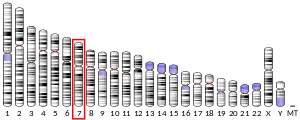

In 1994, a new allele of reeler was obtained by means of insertional mutagenesis.[21] This provided the first molecular marker of the locus, permitting the RELN gene to be mapped to chromosome 7q22 and subsequently cloned and identified.[22] Japanese scientists at Kochi Medical School successfully raised antibodies against normal brain extracts in reeler mice, later these antibodies were found to be specific monoclonal antibodies for reelin, and were termed CR-50 (Cajal-Retzius marker 50).[23] They noted that CR-50 reacted specifically with Cajal-Retzius neurons, whose functional role was unknown until then.

Chromosome region 7q22 that harbours the RELN gene is associated with schizophrenia,[142] and the gene itself was associated with the disease in a large study that found the polymorphism rs7341475 to increase the risk of the disease in women, but not in men. The women that have the single-nucleotide polymorphism (SNP) are about 1.4 times more likely to get ill, according to the study.[143] Allelic variations of RELN have also been correlated with working memory, memory and executive functioning in nuclear families where one of the members suffers from schizophrenia.[142] The association with working memory was later replicated.[144] In one small study, nonsynonymous polymorphism Val997Leu of the gene was associated with left and right ventricular enlargement in patients.[145]